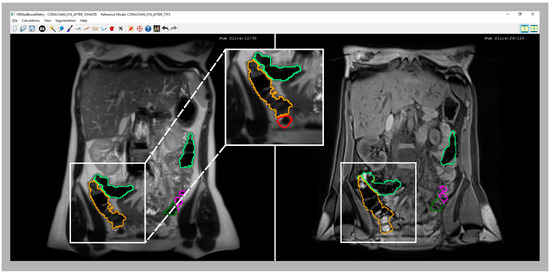

As shown in previous sections, a synchronized visualization of T1-FS and T2 sequences is required to validate the coherence between both colon segmentations and, also, to correct the results in some confusing zones (see an example in Figure 6).

Figure 6.

Comparative images of a confusing area of the cecum in T2 (left image) and T1-FS (right image) sequences. Note that in the T2 sequence, part of cecum was not included in the initial segmentation because it was confused with the small bowel; a zoom (central image) provides a better visualization of the non-included area (red line). However, in the synchronized visualization with the T1 sequence (right image), the feces facilitate the cecum demarcation. Therefore, using the new inspection module, the medical specialist should be able to correct and include the cecum in the final segmentation.

In all the analyzed cases, when the specialist detected a complex area where the colon was difficult to identify using only one sequence (T2 or T1-FS), the analysis of the same area in the other sequence helped him to decide. In general, these confusing areas were located in the T2 images, especially where the small intestine was very close to the colon and their pixel intensities were similar (see Figure 6). The new module facilitates and gives security to the specialists at the time of determining the belonging of the area to the colon. Another complex area was the liver zone, where sometimes the separation between the colon and the liver is not clear enough to determine, accurately, the separation between both anatomical structures. The use of the synchronized navigation helped the specialist to be confident in this decision.